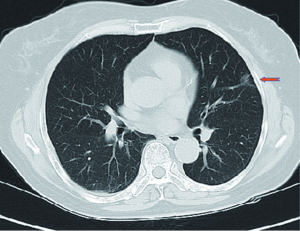

A 64-year-old female presented with a 2.0 cm × 2.0 cm × 1.0 cm nodule in posterior segment of right upper lobe and a ground glass opacity (GGO) in the left upper lobe on computed tomographic (CT) (Figures 1,2) was admitted in our institute on March 16th, 2014. The patient underwent preoperative staging and cardiac and pulmonary function assessment. PET-scan indicates no signs of metastasis. Under general anesthesia with double lumen tube, the patient underwent uniportal cVATS lobectomy for right upper lung tumor on March 19th, 2014 (Figure 3). The final pathologic TNM staging is T1aN0M0 (IA). Regular follow up was initiated for the GGO in the left upper lobe.